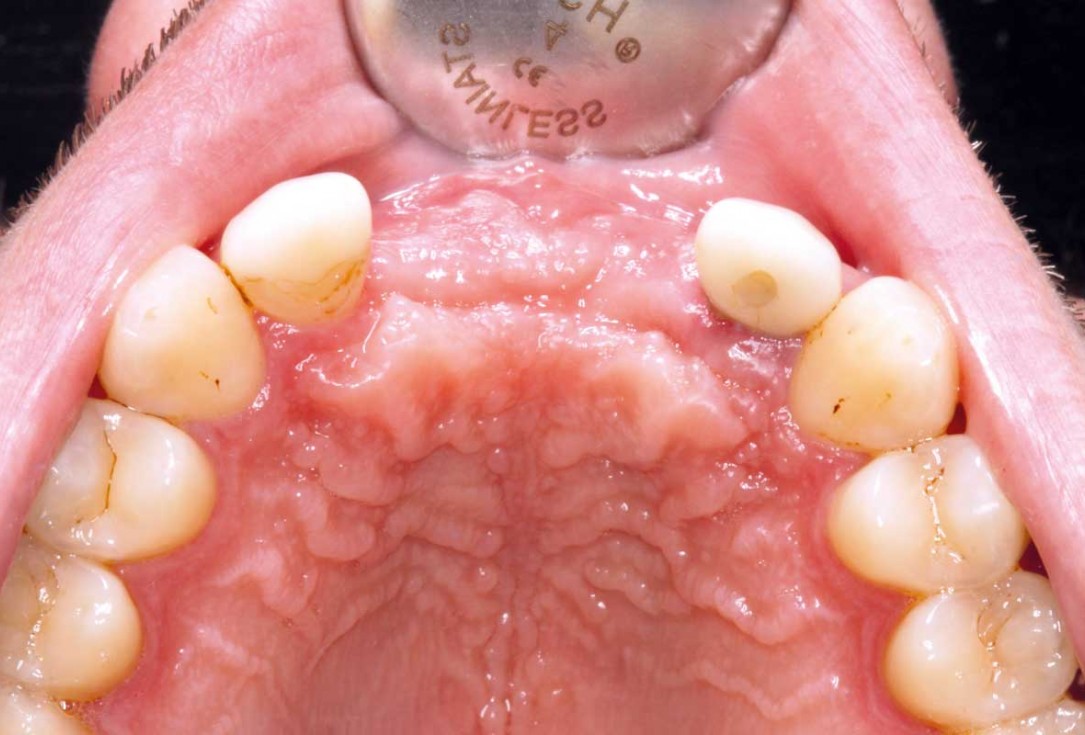

11/26 - Wound healing after 6 months

Ridge augmentation in the maxilla with maxgraft® bonebuilder in the aesthetic zone - Dr. M. Kristensen

12/26 - Clinical situation after 6 months